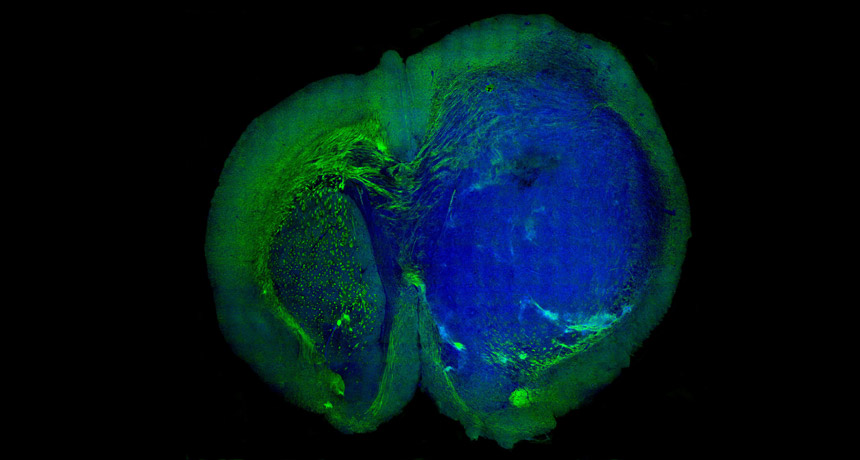

THE CUTTING EDGE  A new technique generates colored images that differentiate tumor tissue (blue) in a mouse brain from surrounding healthy tissue (green). The technique may eventually improve brain surgery.

Ji et al/Science Translational Medicine

A tiny probe equipped with a laser might reveal what the human eye doesn’t always see: the difference between a tumor and healthy tissue.